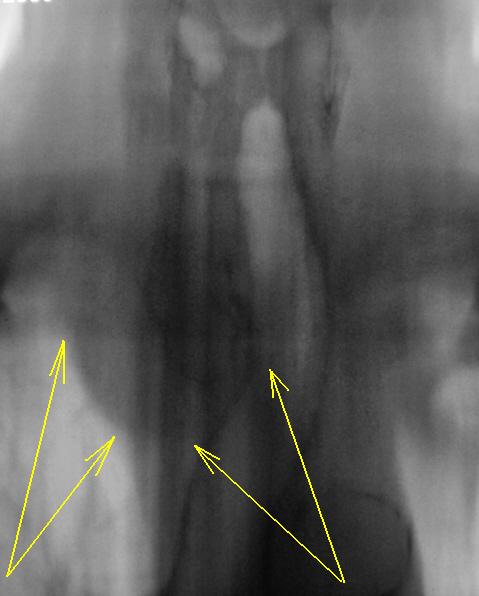

На мой взгляд, слева на верхушке в медиальных отделах верхушеного сегмента (1+2) некоторая динамика есть, да и "кругляк" справа на верхушке (средостении) на 11 срезе, субъективно дифференцируется лучше.

Мне приглянулся последний скан.